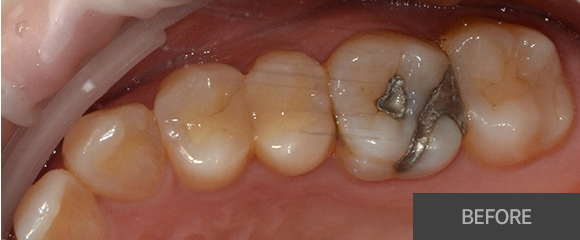

충치치료

레진

인레이

크라운